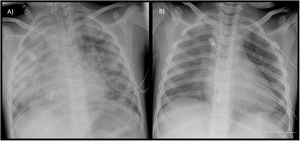

Paciente de género femenino de 5 años de edad con antecedente de neumonías recurrentes bilaterales, que presenta insuficiencia respiratoria aguda, infiltrados pulmonares bilaterales y anemia microcítica (hemoglobina [Hb]: 9,7g/dl; volumen corpuscular medio [VCM]: 67fl). Ingresa en la unidad de cuidados intensivos pediátricos (UCIP) donde se coloca catéter yugular central, sonda vesical y tubo endotraqueal del número 5 para ventilación mecánica. La aspiración de secreciones hemáticas por el tubo endotraqueal decide la realización de broncoscopia flexible con lavado broncoalveolar (LBA), en el que se detecta un 80% de hemosiderófagos. Recibe tratamiento con corticoide intravenoso, resolviéndose el cuadro clínico con normalización de radiografía (Rx) de tórax en 48h (fig. 1). En los meses posteriores al diagnóstico, se administra de mantenimiento bolos intravenosos de metilprednisolona a dosis altas, hidroxicloroquina oral y budesonida inhalada. Debido a reagudizaciones de la enfermedad tras intentos de reducción o suspensión de corticoides sistémicos, y al desarrollo de enfermedad de Perthes secundaria a los mismos, se suspende corticoterapia y se añade azatioprina oral, con buena evolución clínica en la actualidad.